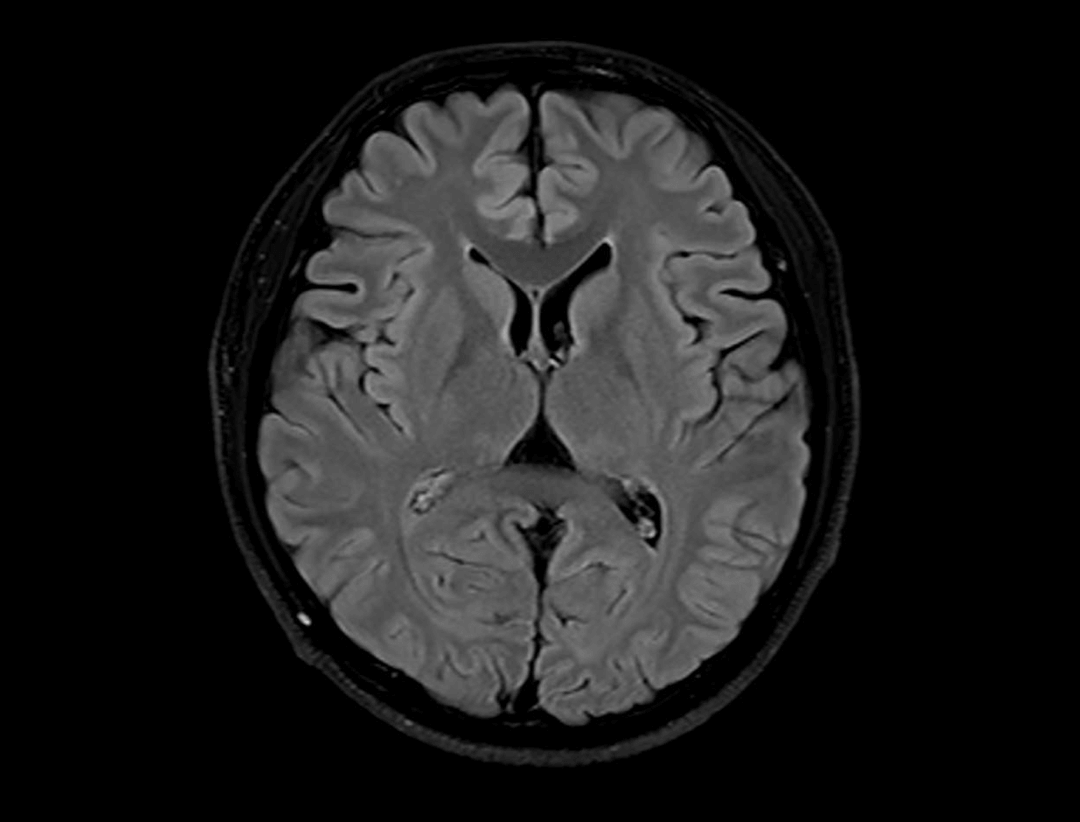

uMR® 770 provides high-speed imaging on all anatomy with significant scan time reduction.

Acceleration technology enables the uMR® 770 to significantly improve scan efficiency and increase patient throughput.